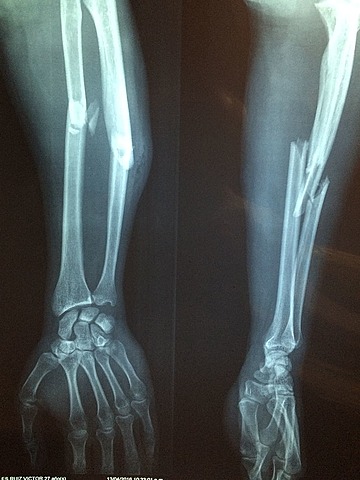

• braç trencat

braç trencat

el dia 15/09/2016 vaig tenir un accident i em vaig trancar el braç